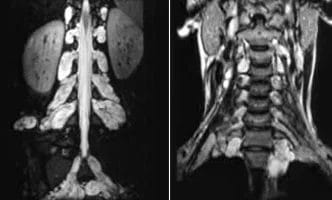

Internal-Carotid-Artery-Stenosis-2

Internal Carotid Artery Stenosis